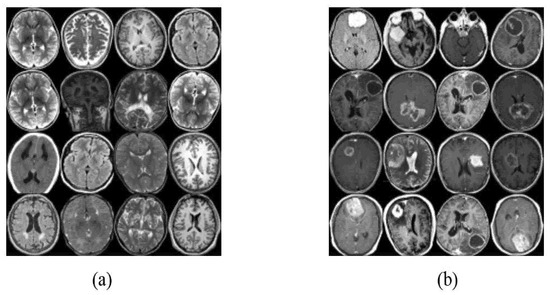

4.1. Datasets of the Study

4.2. Image Augmentation Using Vanilla GAN and DCGAN